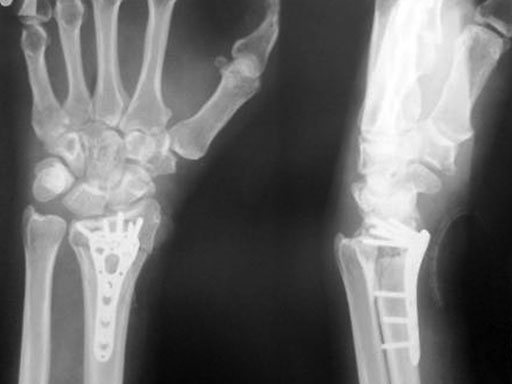

Fig 3a-b Post-op 3 months